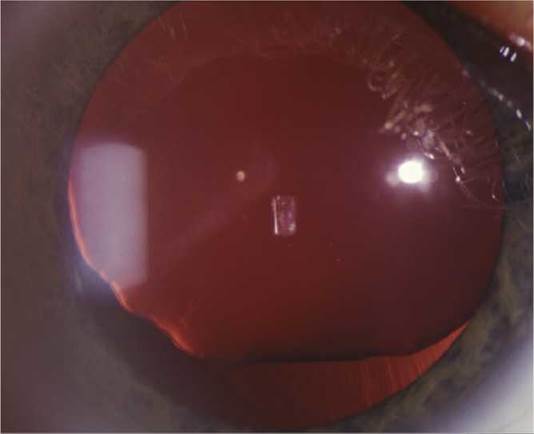

(See Figure 13.1.1.)

FIGURE 13.1.1 Cataract with early cortical changes and nuclear sclerosis.

Critical. Opacification or discoloration of the normally clear crystalline lens.

Other. Blurred view of the retina with dimming or disruption of the red reflex on retinoscopy. Myopic shift from nuclear sclerosis may cause increased near vision—so-called “second sight.” Cataract alone does not cause a relative afferent pupillary defect (RAPD).